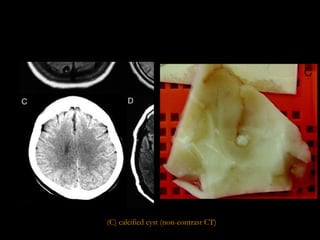

(C) calcified cyst (non-contrast CT)

STAGES OF NC Cystic or vesicular stage Cyst wall & scolex do not enhance  Cyst is viable & has a well defined, fluid-filled membrane contains only one scolex.  Colloid stage Enhancing walls with perilesional oedema Earliest stage in the involution of the cyst. the fluid contents of the cyst become more turbid and the scolex begins to degenerate. Necrotic, granular stage Characterized by parasite necrosis and surrounding inflammation Gives an appearance of an eosinophilic structure in which the bladder and scolex are in various stages of disintegration Oedema and/or necrosis of the surrounding neural tissue may be present in some cases Fibro-calcified nodule With time, fibrosis develops, progressively occupying the entire lesion D.Sharada et al